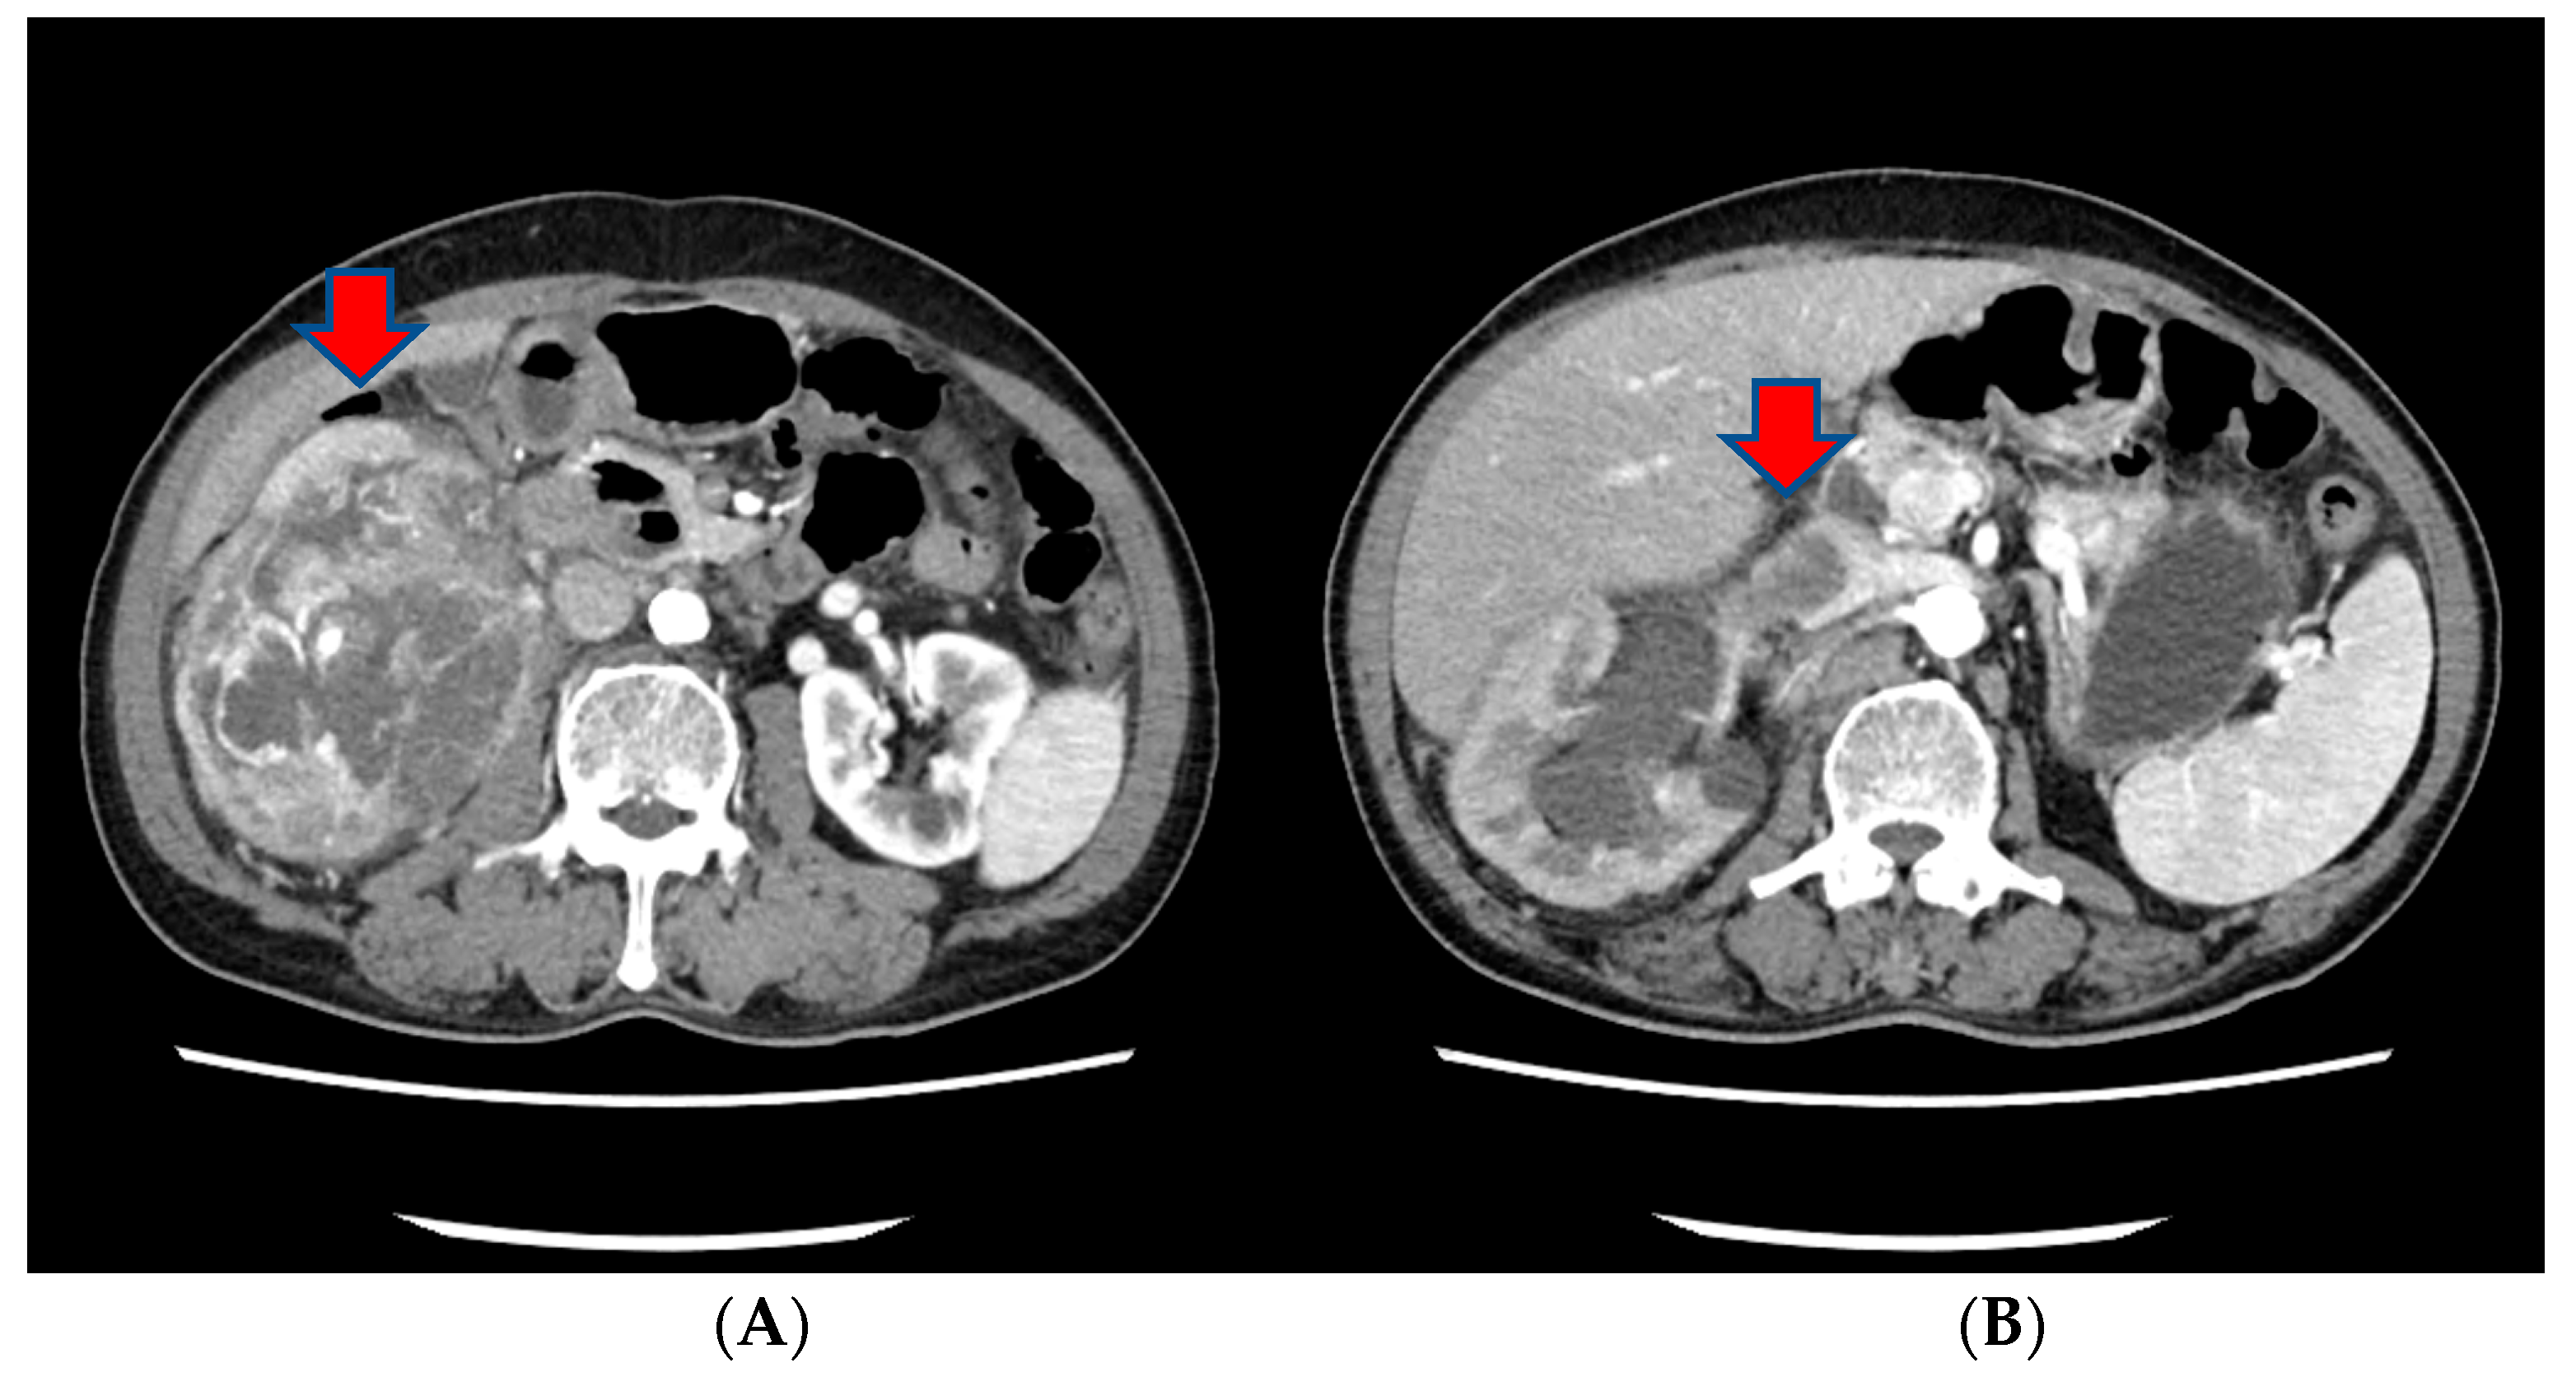

Approximately three months prior to presentation, he sought medical attention for right flank pain and underwent a computed tomography (CT) scan. Before the visit, the patient did not have any significant physiological or medical history. The findings revealed an approximately 13 cm sized heterogeneous mass in the lower pole of the right kidney, exhibiting robust arterial enhancement. It displayed invasion into the adjacent psoas muscle, indicating a potential RCC diagnosis. Additionally, evidence of tumor thrombosis in the inferior vena cava (IVC) was also observed (Figure 1). During the same CT examination, a specific finding of right scrotal varicocele was noted. This was likely attributed to thrombosis and extrinsic compression of the right gonadal vein due to the large mass in the right kidney. CT imaging of the chest showed no evidence of pulmonary mass or adenopathy.

Figure 1.

The CT scan of the abdomen of our patient. (A) An approximately 13 cm sized heterogeneous mass in the lower pole of the right kidney, exhibiting robust arterial enhancement. (B) The finding of tumor thrombosis in the inferior vena cava (IVC).